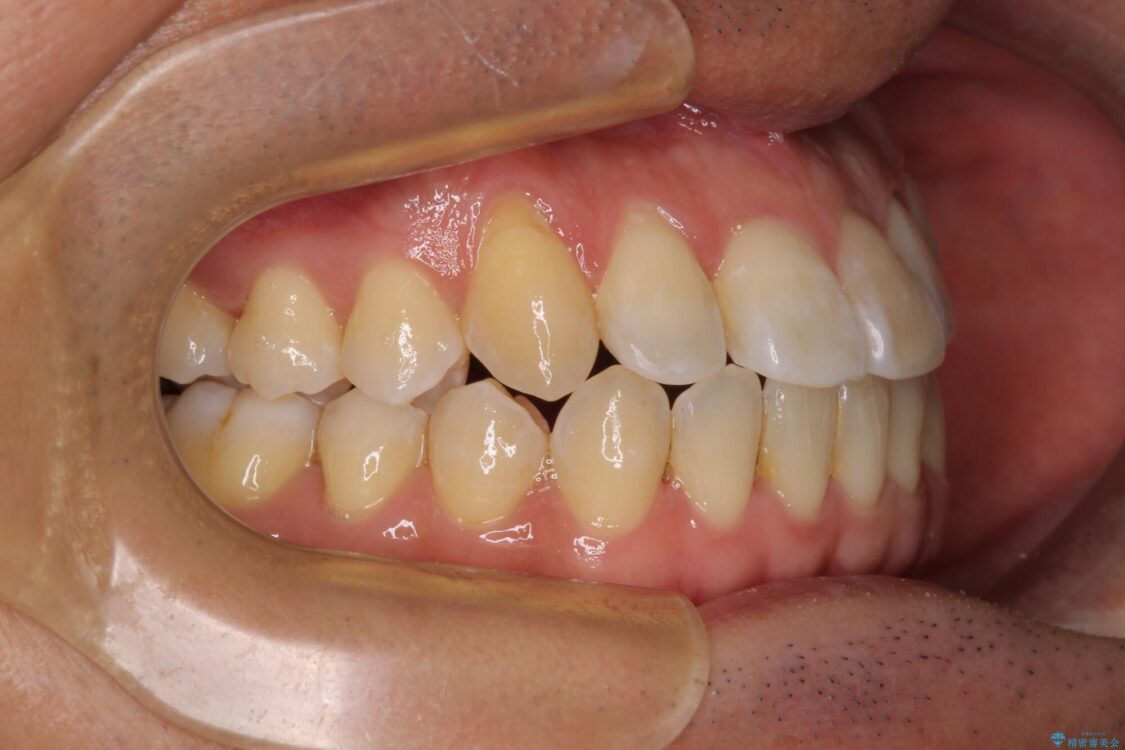

八重歯と前歯のデコボコを気にして来院された患者様です。

治療前

• 左右の八重歯が気になる ワイヤー装置での咬み合わせ改善 治療前画像